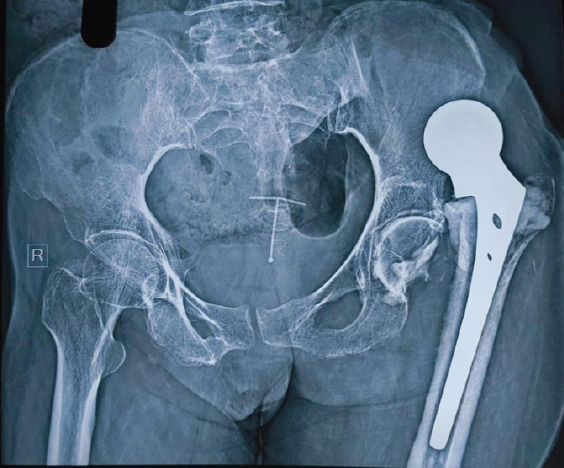

Case report: A 76-year-old woman presented 8 months after left hemiarthroplasty with persistent hip pain and immobility. She had become bedridden 1-month post-surgery following a sensation of hip slippage. Examination revealed limb shortening, adduction deformity, and restricted mobility. Radiographs showed a dislocated hip and multiple dense opacities in the acetabulum, suggesting cement interposition. A posterior approach revision was planned. Pre-operative skin traction and adductor tenotomy were performed to address soft tissue contractures. Intraoperatively, well-formed cement mass conforming to the acetabulum was removed. The cement was removed en bloc, and a bipolar prosthesis was implanted. Post-operatively, the patient achieved satisfactory recovery with improved hip stability and function.

Discussion: This case illustrates the potential for cement to migrate into the acetabulum during stem insertion if introduced pre-maturely or in excess. Such interposition disrupts joint articulation and can lead to chronic dislocation. Preventive steps - such as waiting for appropriate cement consistency, using a gauze barrier in the acetabulum, and careful intraoperative assessment - are critical to avoid such outcomes. Chronic dislocations further complicate surgical revisions due to soft tissue contractures and biomechanical imbalance. Comprehensive pre-operative planning and soft tissue management, combined with appropriate implant selection, contributed to successful revision in this case.